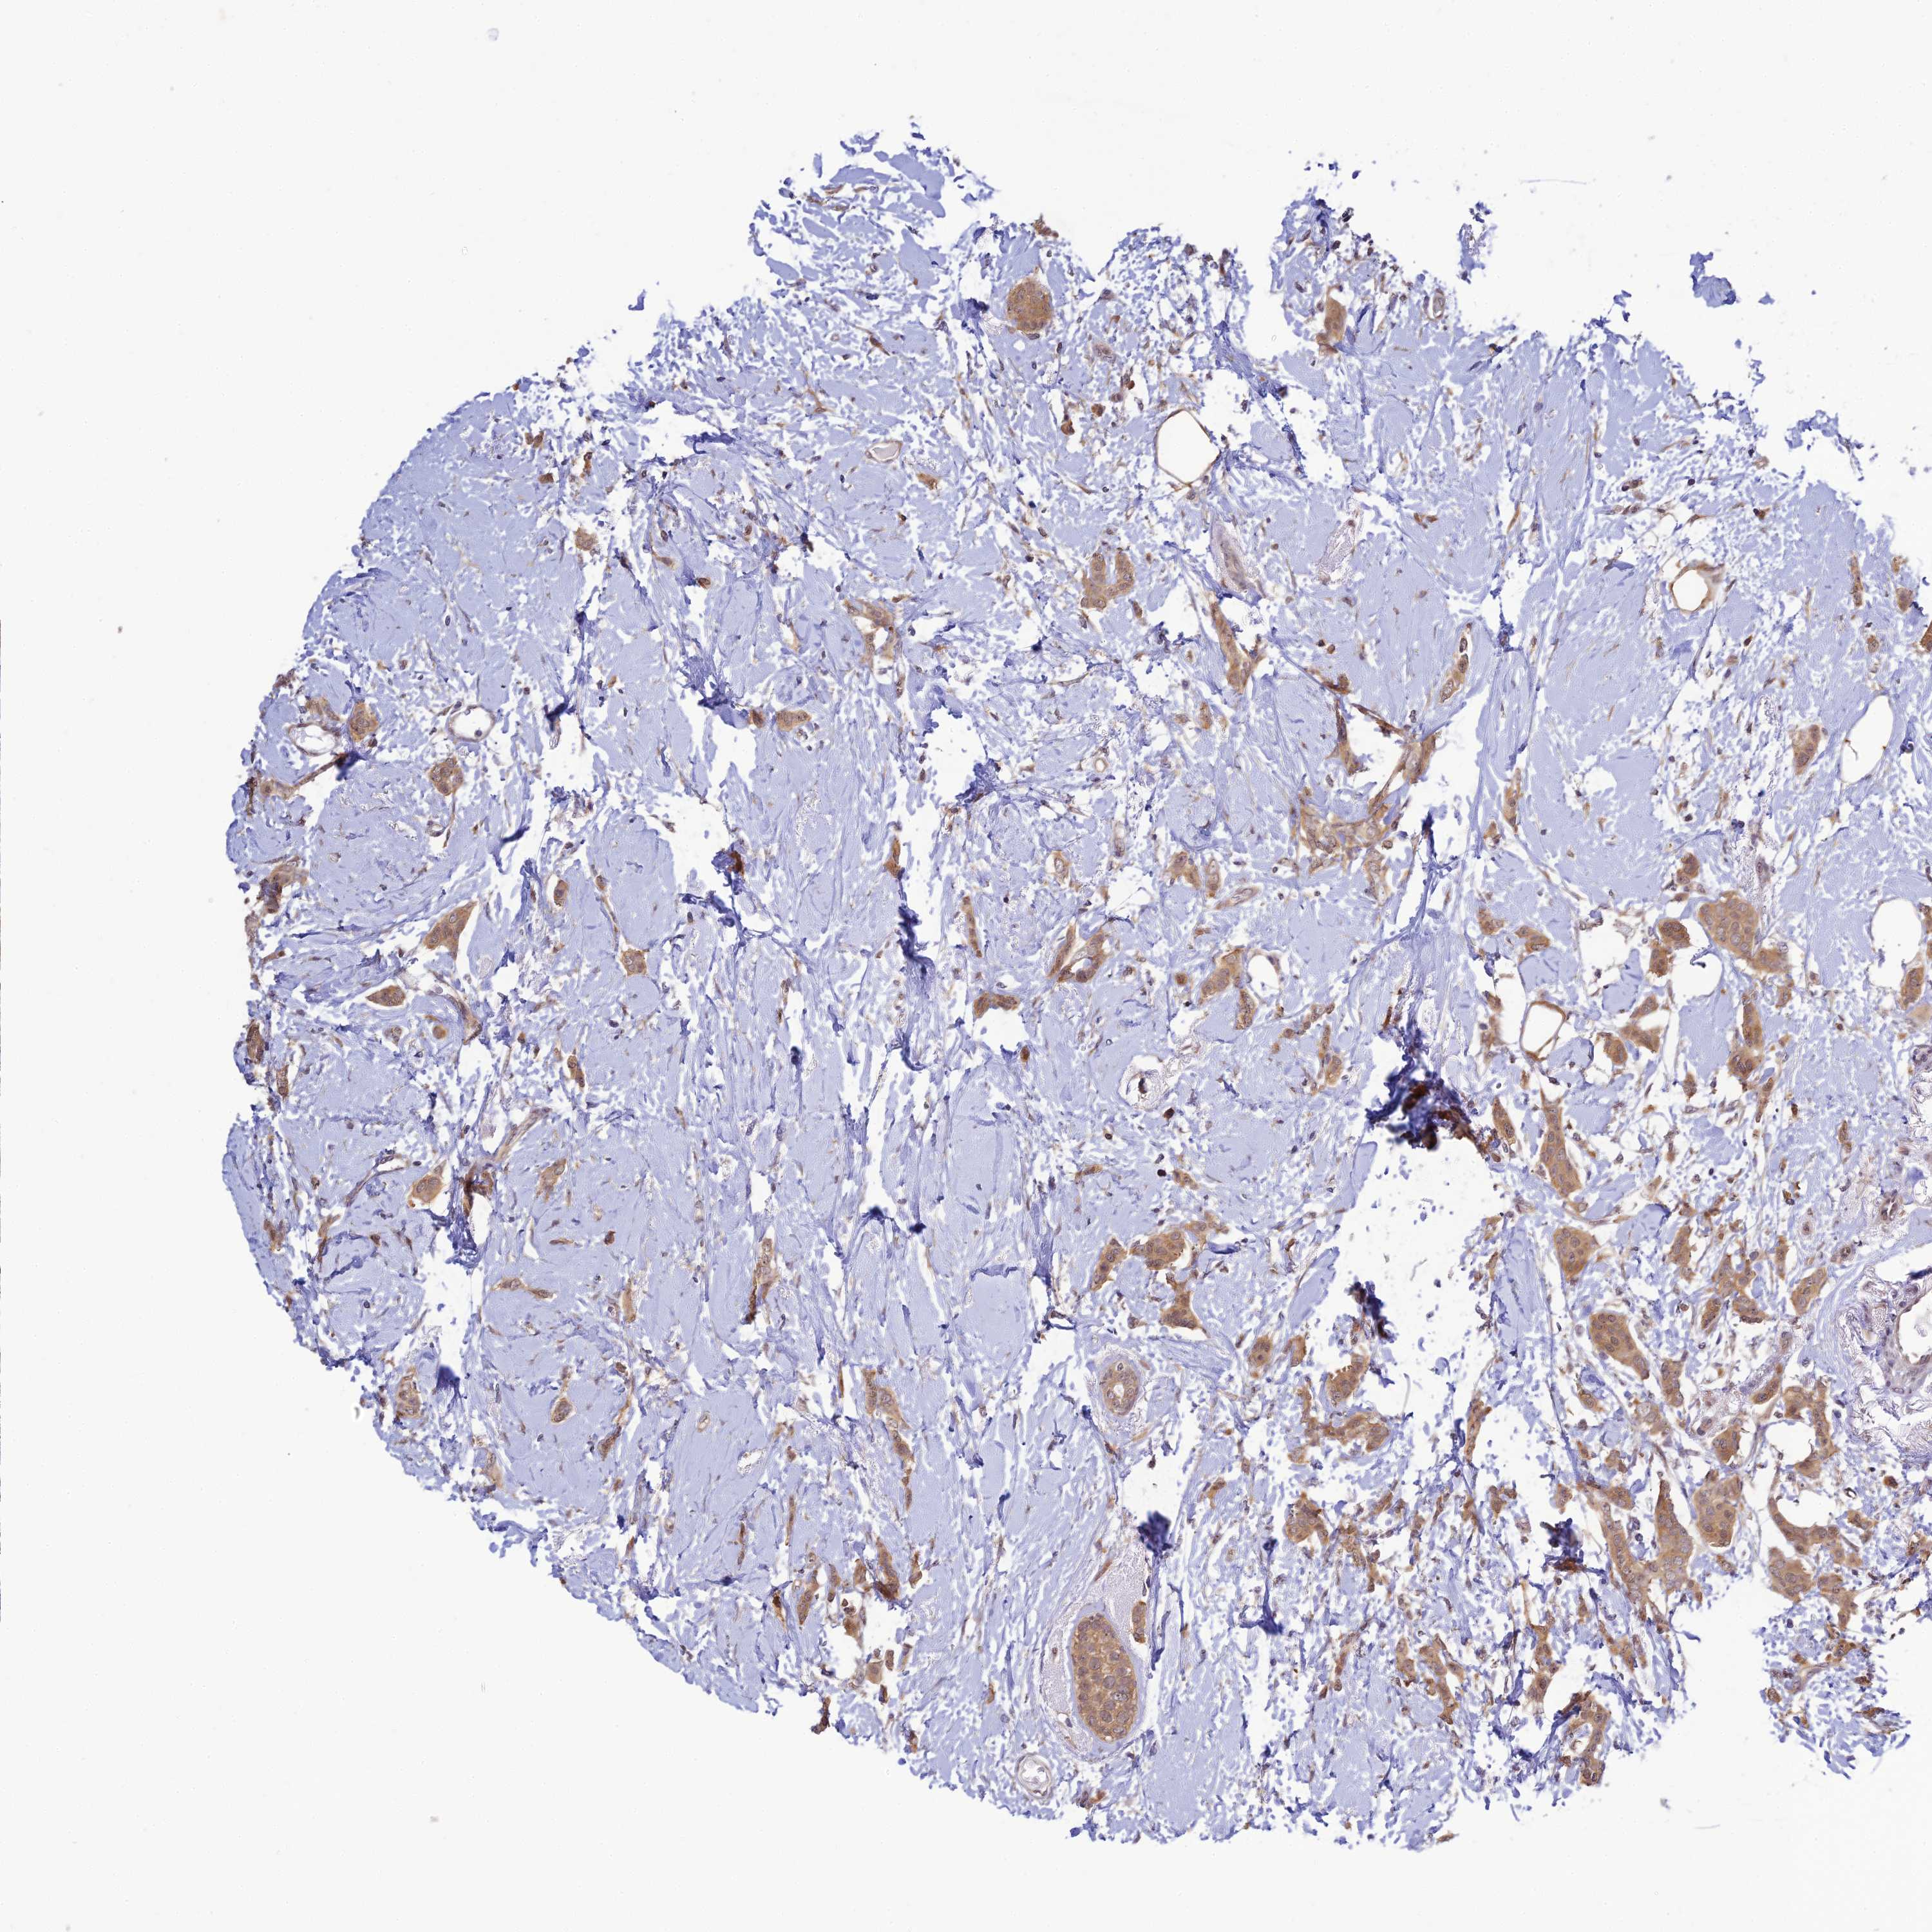

CANCER BREAST CANCER Show tissue menu

BRCA TCGA BRCA VALIDATION PROTEIN EXPRESSION